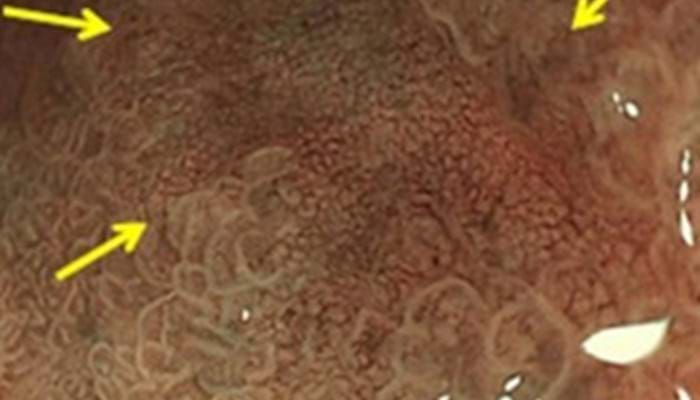

Narrow Band Imaging

Rashid Hospitalalso uses Narrow Band Imaging (NBI), a technology that helps to diagnose minute pre-cancerous lesions via endoscopy which could then be removed within the same appointment; this eliminates the need for surgery in most cases, and with a very low risk of complication.